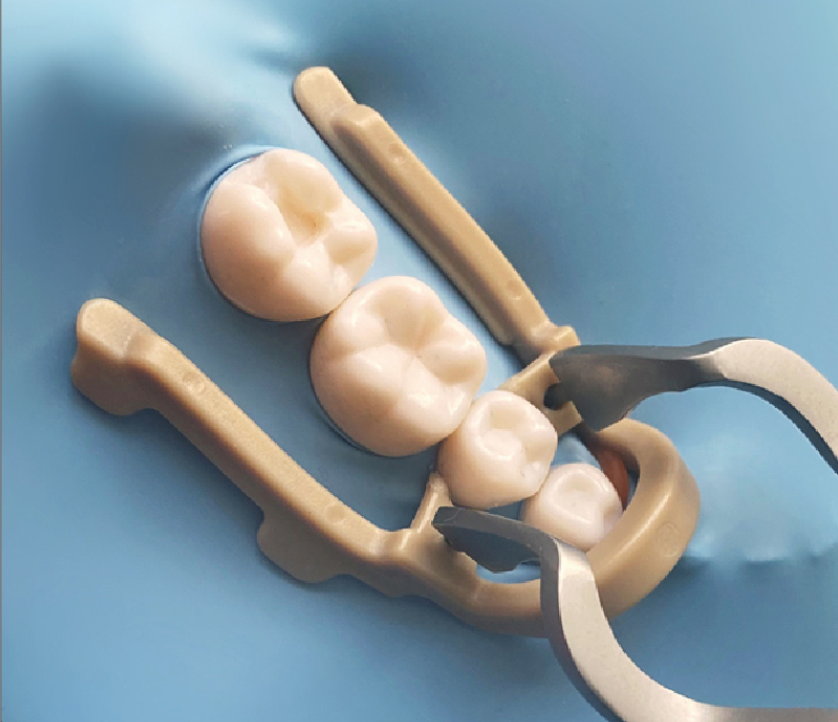

Para fijar el dique de muelas en casos de restauraciones de clase II con extensión distal.

Coloque la pinza en el premolar con unas pinzas para dique de muelas.

Al utilizar el dique de muelas en la extensión distal, la pinza fija el dique de muelas y ayuda a dejar suficiente área de tratamiento